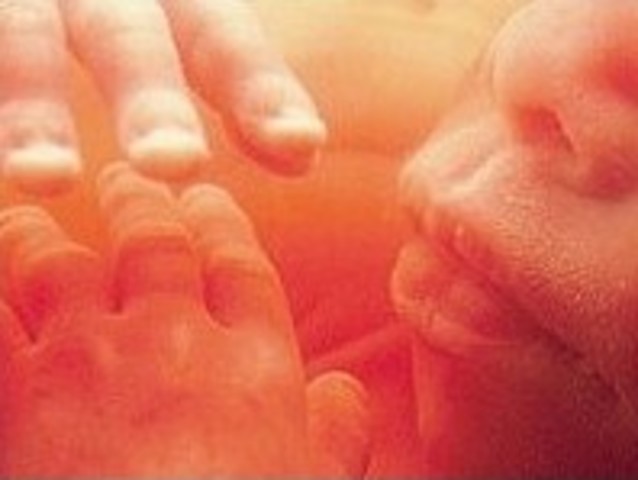

• Week 8

Week 8

The embryo now has little arms and legs in place, fingers and toes are visible. It is about 18mm and it begins to practice movement.